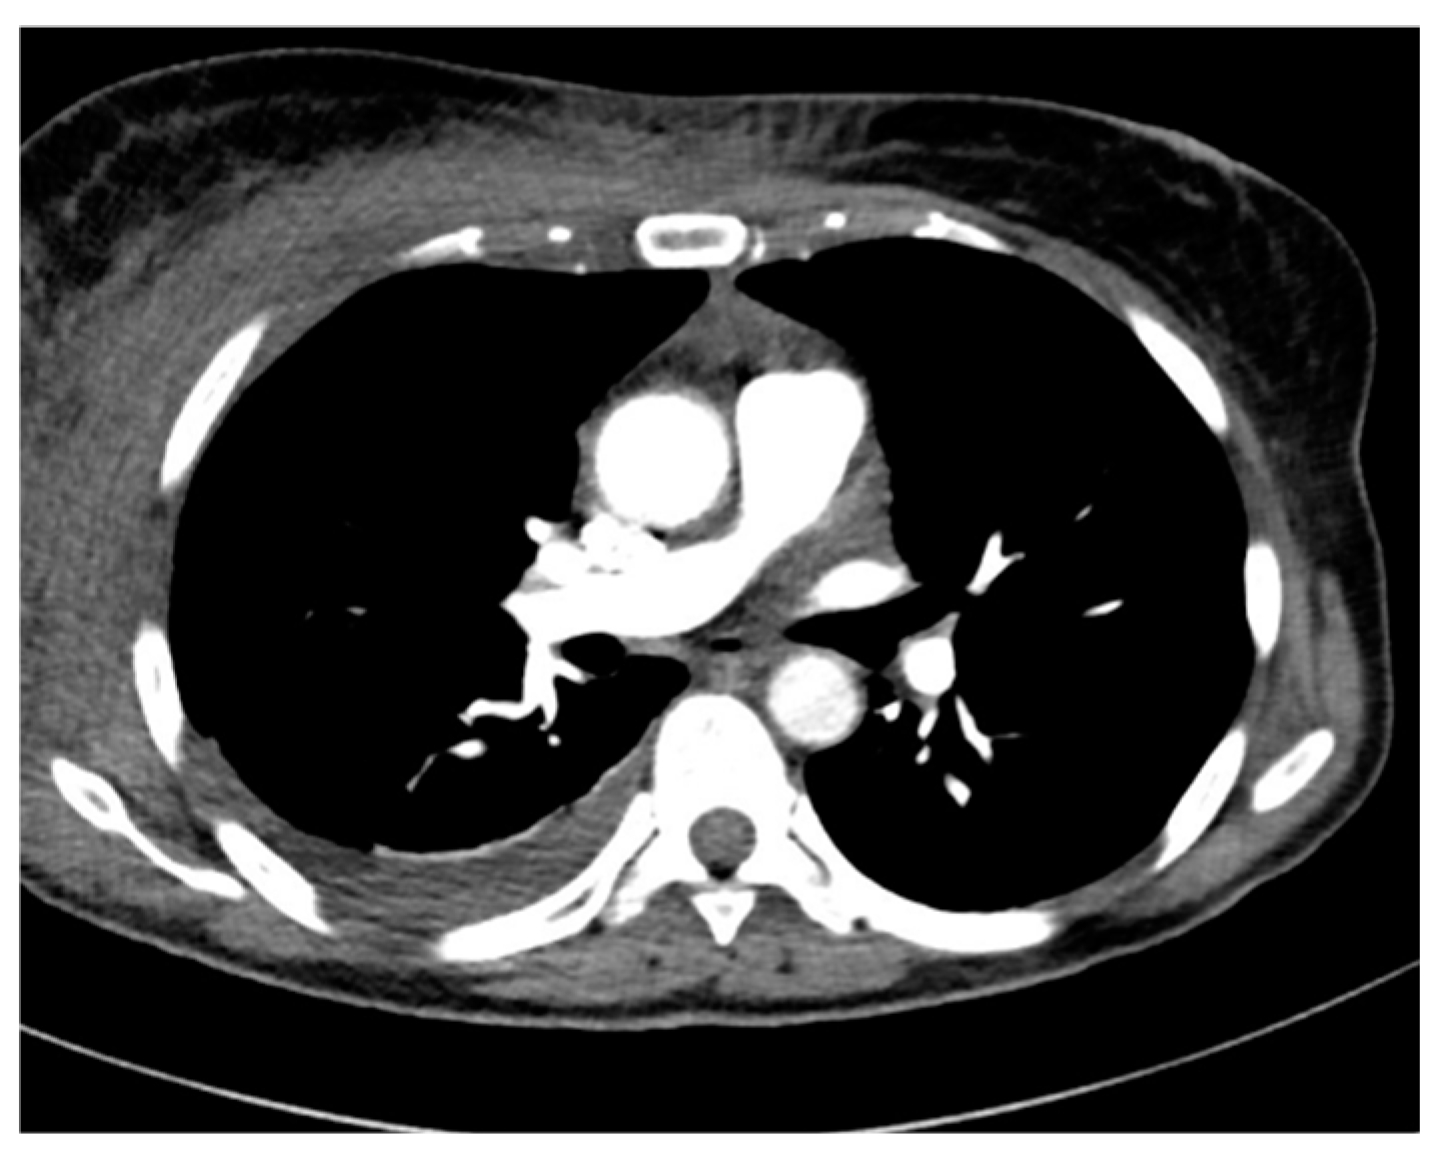

| 1 | 42/M | Upper respiratory tract infection | none | AH1N1 flu virus | 41 | 15 | yes | 7 h | Died |

| 11 | 35/M | Pneumonia ARDS | none | Rhinovirus/Enterovirus (PN+) c | 21 | 15 | yes | 19 days | Transferred to the transplant center |

| 1 | Yes | no | blood culture bronchoalveolar lavage | Levofloxacin Vancomicin | none |

| 11 | Septex ECMO c | no | sputum + (PN+) d | Ertapenem Linezolid | Ertapenem Linezolid Penicillin |